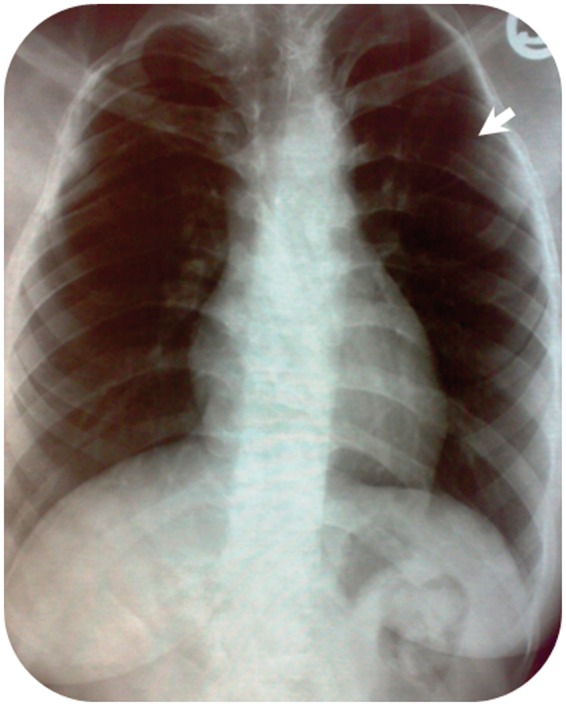

A 15-year-old girl was referred to a dentist complaining of parageusia, bad taste in the mouth, which started 9 months ago. Panoramic X-ray and non-enhanced computed tomography scan revealed multiple bilateral unilocular cysts in the mandible and maxilla, along with calcification of anterior part of the falx cerebri. She was eventually diagnosed with Gorlin-Goltz syndrome based on imaging and histopathologic finding of keratocystic odontogenic tumor.